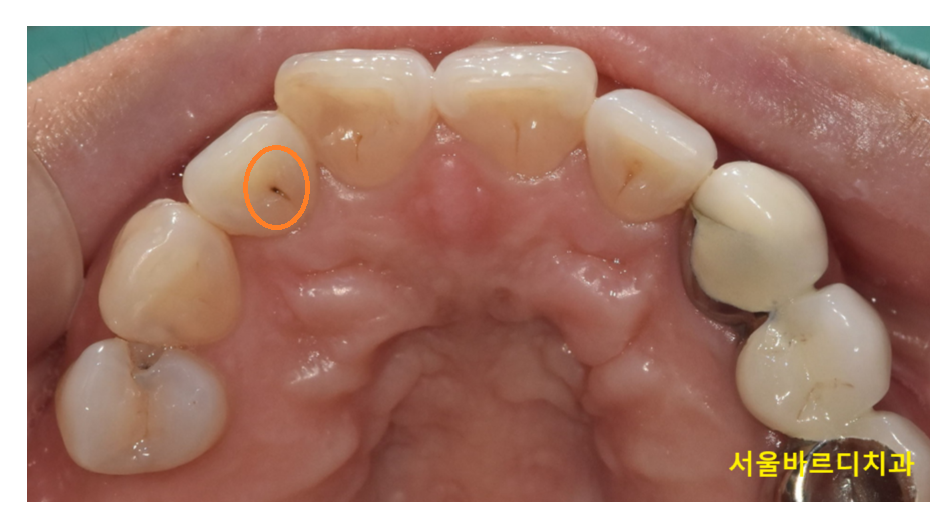

250120 치아 사이에 충치가 생겼어요!

특히 얕은 충치의 경우에는 검사 시 발견되는 것이 대부분입니다.